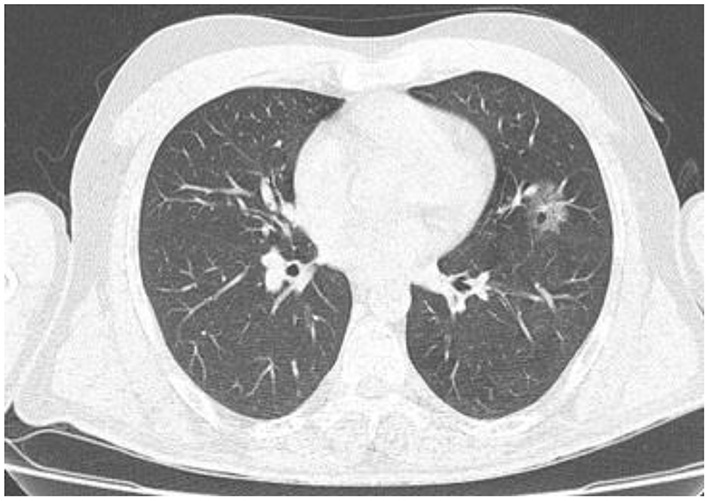

In the present study, 160 males and 70 females were enrolled to explore the association of lung CT findings in COVID-19 with patients' age, body weight, vital signs, and medical regimen. The reported major lung CT scan findings were GGO in 47 (20.4%) patients; calcified nodules in 3 (1.3%) patients; atelectasis and fibrotic band in 16 (7.0%) patients; pleural effusion and consolidation in 22 (9.6%) patients; infiltration and pneumonia in 11 (4.8%) patients; and emphysematous changes in 11 (4.8%) patients of the study sample (230 participants). Three different cases with major lung changes are shown in Figures 1–3. However, one case with minor lung CT scan findings is shown in Figure 4.

Figure 4. High resolution, axial non-enhanced spiral chest CT image (lung window) of a 44-years old patient who was confirmed to be infected by COVID-19 and admitted to hospital with no symptoms (asymptomatic). CT image shows only a small ground-glass pattern in the lower aspect of the anterior segment of the upper lobe of the left lung.